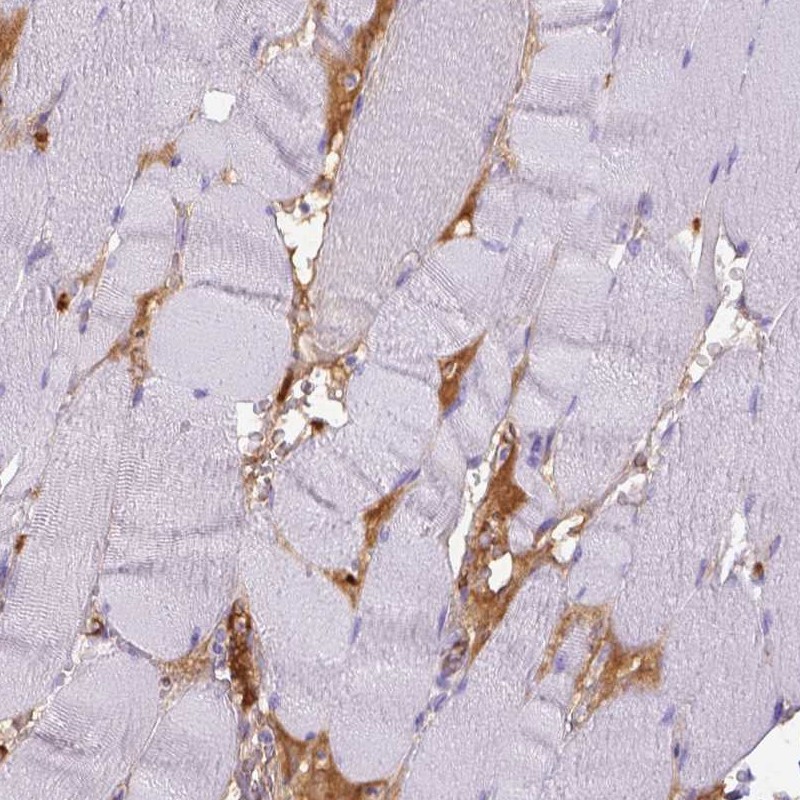

Immunohistochemistry analysis in human skeletal muscle and colon tissues using Anti-ITIH4 antibody. Corresponding ITIH4 RNA-seq data are presented for the same tissues.